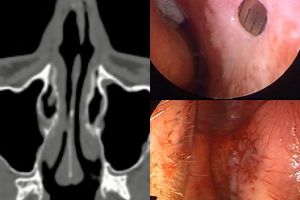

В первом случае была спонтанная перфорация размером 2 на 1,7 см у любителя "ковыряться" в носу. Пациента помимо сухости и образования корочек беспокоили носовые кровотечения. Фото 1, 2.